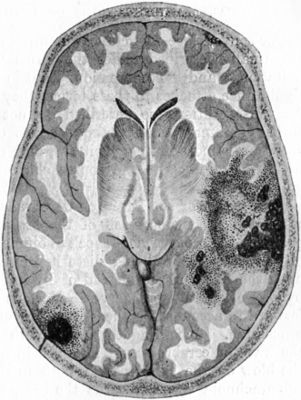

184.Contusion and Laceration of Brain343